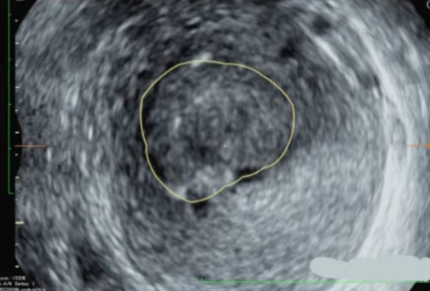

肌瘤类型和位置经评估适合做USgFUS。

MRI

USgFUS为子宫肌瘤患者提供了一种革命性的无创治疗选择,尤其适合有保宫需求、恢复时间要求高的女性。但它不是“万能神器”,其成功高度依赖于严格的术前影像评估和患者选择。